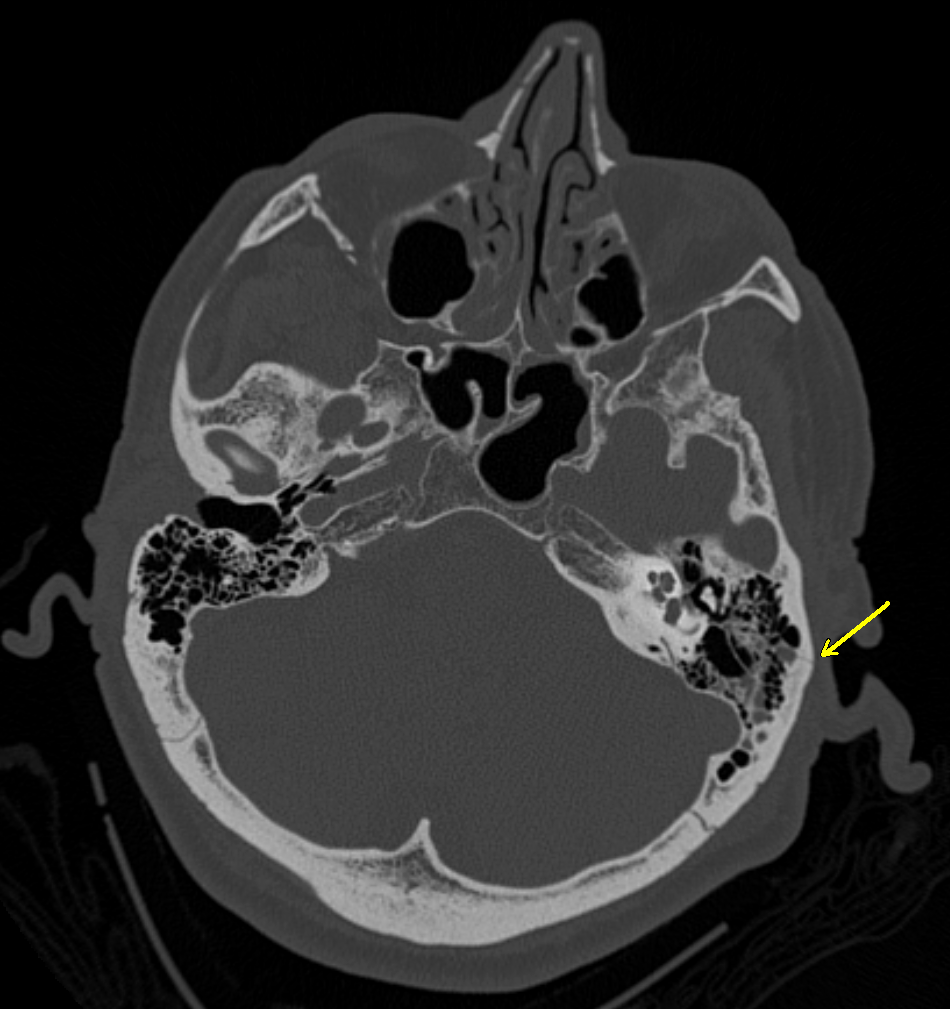

Ct skull base anatomy. You can however go directly to any section using the links below. B axial ct image with color coded overlay shows the skull base bones. The skull base can be evaluated by computed tomography ct which will demonstrate the bony structures of the skull base with its foramina and fissures for vessels and cranial nerves the temporal bone and sinonasal cavities.

Ct anatomy of skull base. Blue central skull base csb purple posterior skull base teal anterior skull base asb. Foramina of the skull base and the structures that pass through them.

Cranial foramina for further details. A axial three dimensional reconstructed ct image with color coded overlay shows the skull base sections. Ct anatomy of skull base.

The base of the skull is perforated by numerous foramina which allow vessels and nerves to pass through the base of the skull allowing the intracranial cavity to communicate with the rest of the body see main article. Skull ct anatomy the sagittal suture is the line where the right and left parietal bone are in contact. A noncontrast sinus or skull base ct which covers the mastoids temporal bone and entire skull base is recommended and intravenous contrast is not usually necessary as the mri will provide soft tissue detail.

Ct is more sensitive in detecting fibro osseous skull base lesions calcification and sclerosis. The module interface is meant to mimic a radiology workstation with adjacent image scrolling via arrow keys and or mouse wheel button. Navigating the skull base identify the petro occipital fissure to navigate the major structures of the skull base.